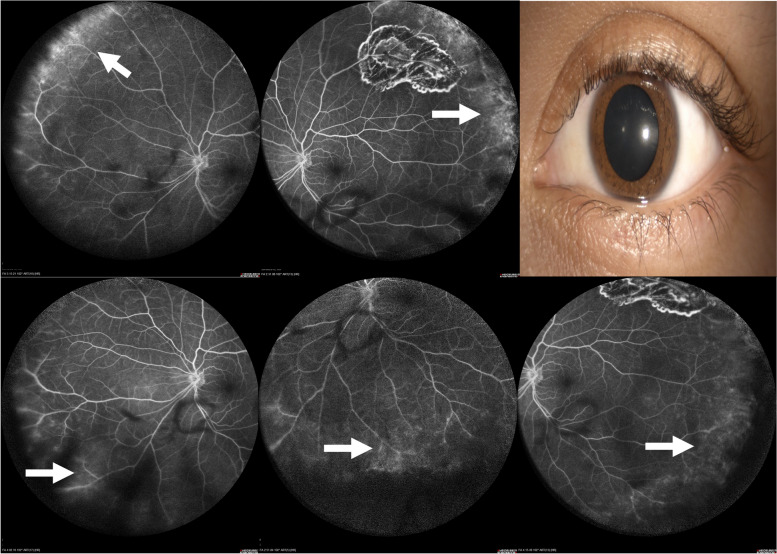

目的:描述在活动性前巩膜炎患者中出现宽视场荧光素血管造影(WFFA)的比例。方法:对活动性前巩膜炎患者的WFFA检查结果进行观察性、描述性、横断面研究,包括结节性、弥漫性或坏死性受累。研究使用海德堡光谱仪模块(102º)进行。图像由两位蒙面的共同作者保存和评估。结果:39例患者79只眼,女性31例(79%),平均年龄50.5岁±13.98岁。平均最佳矫正视力(BCVA)为0.1343±0.2475 logMar或20/27。39.58%的活动性巩膜炎眼和16.66%的非活动性巩膜炎眼存在WFFA。全身相关性为50%,与anca相关的血管炎最为普遍。WFFA结果在前弥漫性巩膜炎病例中更为常见,并与中枢性和外周性巩膜渗漏的巩膜严重程度相关(p结论:近40%的前巩膜炎患者有血管渗漏的WFFA结果,无巩膜炎的患者有16%。视网膜血管渗漏需要作为前巩膜炎患者局部和/或全身性活动的标志进行探索,并可能对疾病的严重程度和管理产生影响。

Objective: Describe the proportion of patients with wide-field fluorescein angiographic (WFFA) findings in patients with active anterior scleritis.

Methods: An observational, descriptive, cross-sectional study of the WFFA findings of patients with active anterior scleritis including nodular, diffuse, or necrotizing involvement was performed. Studies were performed with the Heidelberg Spectralis module (102º). Images were saved and assessed by two masked co-authors.

Results: Seventy-nine eyes from 39 patients, 31 (79%) females with a mean age of 50.5 years ± 13.98. Mean best-corrected visual acuity (BCVA) of 0.1343 ± 0.2475 logMar or 20/27. WFFA findings were observed in 39.58% of eyes with active scleritis and in 16.66% of eyes without scleritis. Systemic association was present at 50%, with ANCA-associated vasculitis being the most prevalent. WFFA findings were more frequent in cases of anterior diffuse scleritis and correlated with scleritis severity when central and peripheral leakage (p < 0.022) and cystoid macular edema (p < 0.013) were present.

Conclusions: Almost 40% of eyes with anterior scleritis have WFFA findings of vascular leakage and 16% of eyes without scleritis. Retinal vascular leakage needs to be explored as a sign of local and/or systemic activity in patients with anterior scleritis and may have implications for disease severity and management.